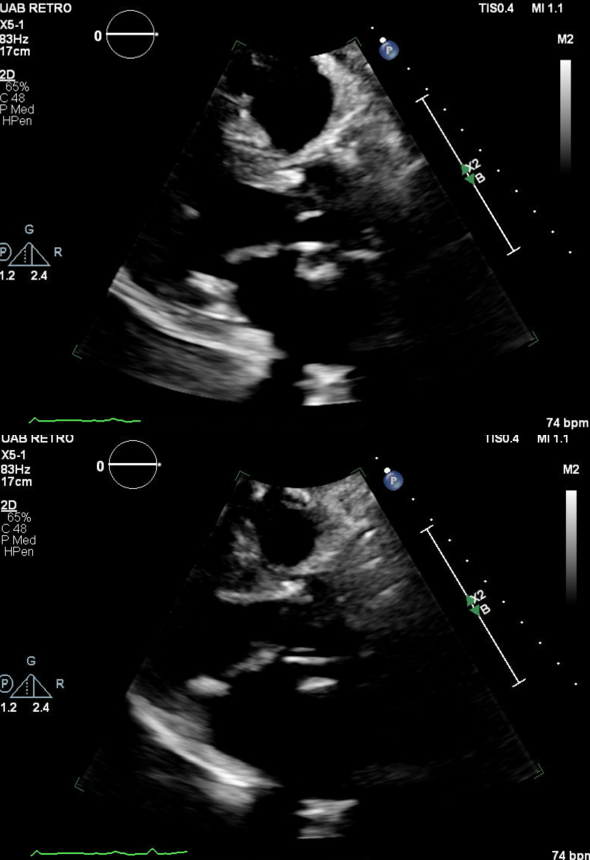

A 74-year-old male developed severe intraoperative vasoplegia following surgical aortic valve replacement, ascending aortic replacement, and coronary artery bypass grafting. He was separated from cardiopulmonary bypass without issue, but cardiopulmonary collapse occurred with transfusion of protamine, fresh frozen plasma, and platelets. He was treated for presumed anaphylaxis with inotropes, steroids, and angiotensin II. While this collapse was initially attributed to transfusion reaction, subsequent investigation revealed a diagnosis of AGS. He was treated with diet restrictions and omalizumab outpatient and his bioprosthetic valve has demonstrated no signs of early failure.

AGS should be considered in anaphylactic patients who receive intra-procedural heparin. The manifestation of alpha-gal-related allergies is uniquely inconsistent in timing and severity. Long-term clinical and echocardiographic surveillance are warranted to monitor for accelerated coronary disease and early bioprosthetic failure.